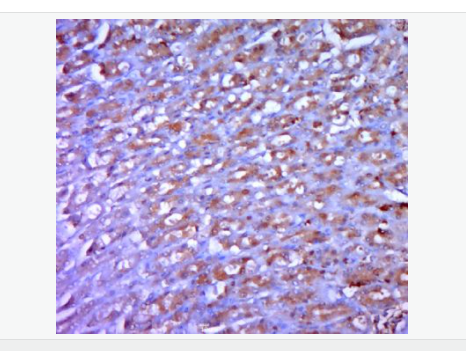

| 产品应用 | WB=1:500-2000 ELISA=1:5000-10000 IHC-P=1:100-500 IHC-F=1:100-500 ICC=1:100-500 IF=1:100-500 (石蜡切片需做抗原修复) not yet tested in other applications. optimal dilutions/concentrations should be determined by the end user. |

| 产品介绍 | The protein encoded by this gene is a member of the bone morphogenetic protein (BMP) family and the TGF-beta superfamily. This group of proteins is characterized by a polybasic proteolytic processing site which is cleaved to produce a mature protein containing seven conserved cysteine residues. The members of this family are regulators of cell growth and differentiation in both embryonic and adult tissues. This gene is thought to encode a secreted protein which negatively regulates skeletal muscle growth. Acts specifically as a negative regulator of skeletal muscle growth. [SUBUNIT] Homodimer; [TISSUE SPECIFICITY] Expressed specifically in developing and adult skeletal muscle. Weak expression in adipose tissue. Belongs to the TGF-beta family. Function: Acts specifically as a negative regulator of skeletal muscle growth. Subunit: Homodimer; disulfide-linked. Interacts with WFIKKN2, leading to inhibit its activity. Interacts with FST3. Subcellular Location: Secreted Tissue Specificity: Predominantly expressed in muscle. At hatching, expression is strongest in the skin epithelium, and is also found in the retina and brain. From day 28, expressed in skeletal muscle. In the adult, highest expression is seen in the gastrointestinal tract, brain, muscle, heart and testis. Also expressed in the adult pharynx, kidney, spleen, liver, gill, eyes, skin, swim bladder and ovary. DISEASE: Defects in MSTN are the cause of muscle hypertrophy (MSLHP) [MIM:614160]. MSLHP is a condition characterized by increased muscle bulk and strength. Affected individuals are exceptionally strong. Similarity: Belongs to the TGF-beta family. SWISS: O14793 Gene ID: 2660 Database links: Entrez Gene: 2660 Human Entrez Gene: 17700 Mouse Omim: 601788 Human SwissProt: O14793 Human SwissProt: O08689 Mouse SwissProt: O18830 Sheep Unigene: 41565 Human Unigene: 3514 Mouse Unigene: 44460 Rat Important Note: This product as supplied is intended for research use only, not for use in human, therapeutic or diagnostic applications. GDF-8又称MSTN,是转化生长因子超家族,也是近年来发现的一类重要的肌细胞生长调控因子,它通过抑制MyoD家族成员转录活性负向控制肌细胞的生长发育,它的表达量与肌肉重量的变化呈负相关。 |